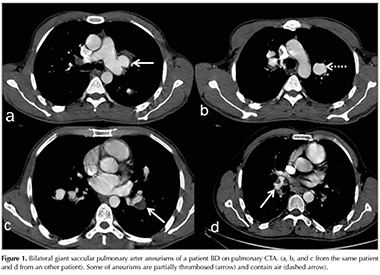

PAA and PAT are the two common presentations of PAI related to BD due to inflammation of the vessel walls (Figure 1). Mural thrombosis in the vein lumen causes intraluminal filling defects consistent with occlusion or stenosis, characteristic of PAT. PAAs are fusiform or saccular dilations of vessels enhancing simultaneously with PA. BD is the most common underlying pathology in patients with PAAs (11). PAAs may consist of partial thrombosis or air bubbles. In their study, Seyahi et al. reported that PAA patients may also have PAT findings, and 8 patients revealed isolated PAT signs among 34 patients with PAA in their cohort (11). In our study, all patients with PAA demonstrated concomitant PAT findings. In addition our study included more isolated PAT cases than PAA (PAA 4, isolated PAT 8). In our patients, right lower lobe artery was the most frequent site of aneurysms, similar to others' reports (11-13).